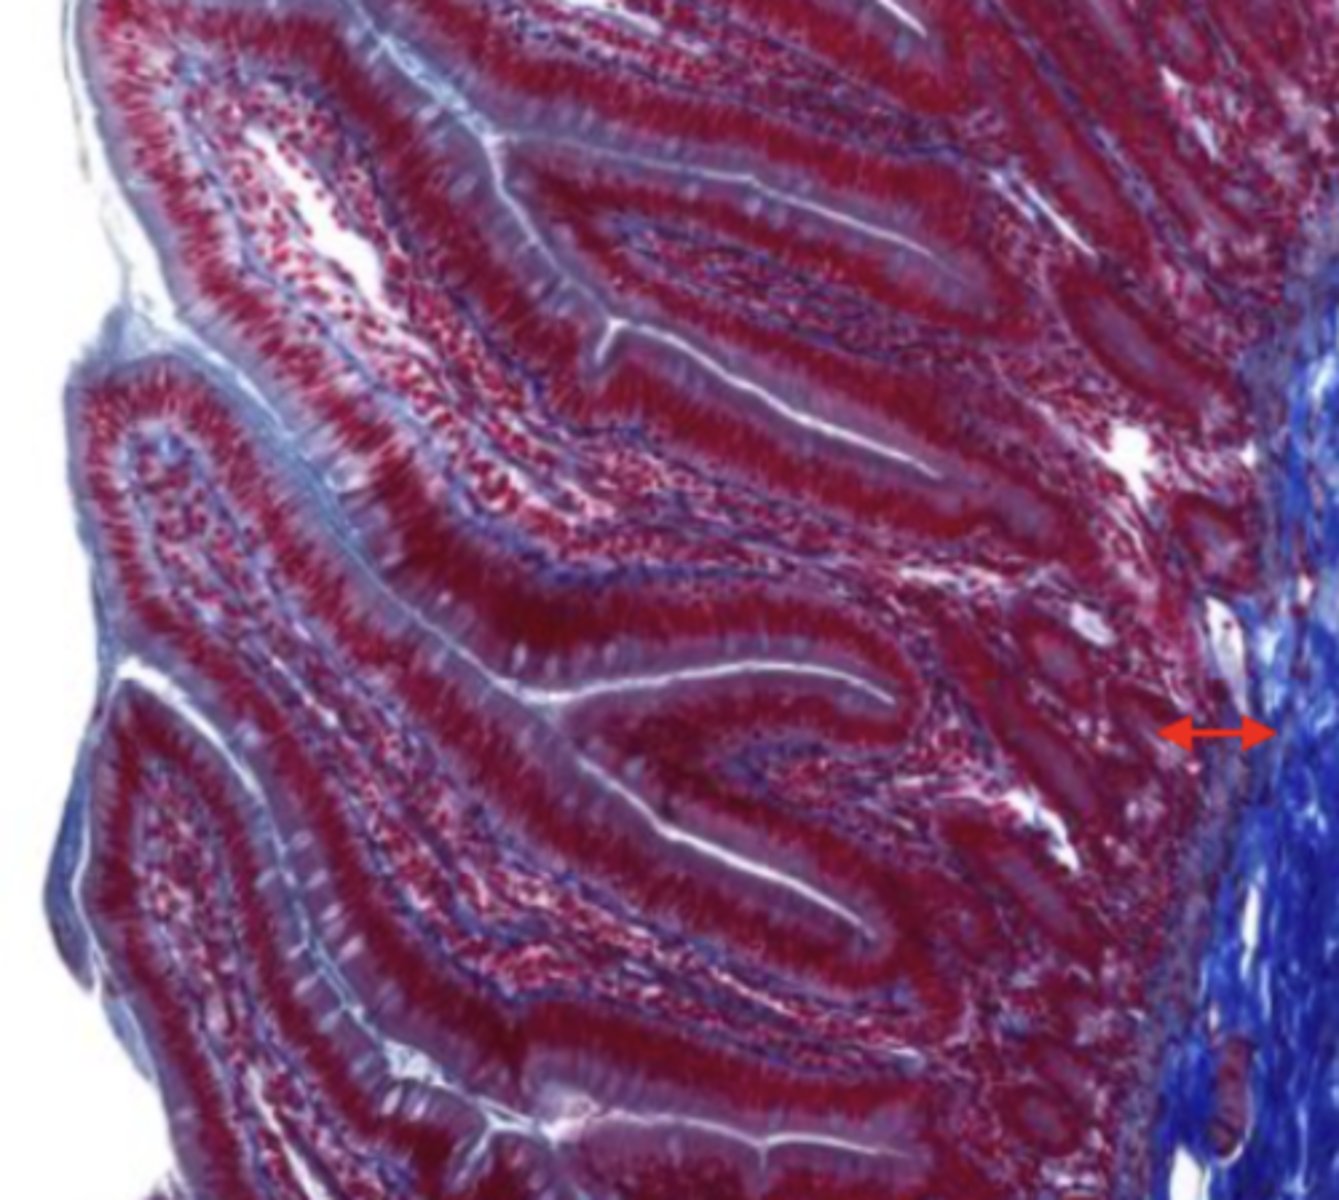

mucosa (esophagus)

mucosal epithelium (esophagus)

stratified squamous epithelium

lamina propria (esophagus)

muscularis mucosa (esophagus)

submucosa (esophagus)

contains glands and blood supply

muscularis externa (esophagus)

serosa/adventitia (esophagus)

gallbladder (histology)

gallbladder

this tissue's wall structures/layers are different than the rest of the organs

simple columnar epithelium

what kind of epithelium lines the mucosa of the gallbladder

lumen (gallbladder)

mucosa (gallbladder)

mucosal epithelium (gallbladder)

lamina propria (gallbladder)

muscularis mucosa and submucosa

gallbladder tissue does not have _______ and ______

muscularis externa (gallbladder)

serosa/adventitia (gallbladder)